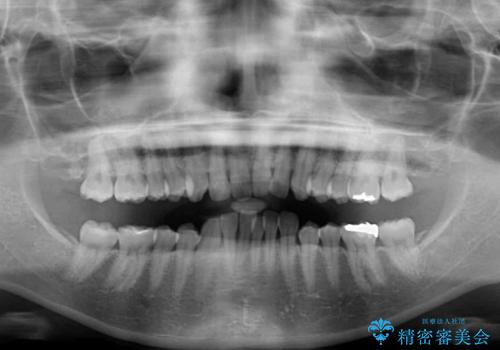

インビザラインによるディープバイトの改善

- 口元の前突感と深い咬み合わせ(ディープバイト)を気にして来院された患者様です。

インビザラインによる上下歯列の遠心移動(後方移動)と、それに伴う近心傾斜(前方傾斜)の改善により、口元の突出感とディープバイトを改善することとしました。

咬合状態が大きく変化したため、治療後半では咬み合わせの位置が定まらなくなりました。上下の前歯に後戻り防止用のワイヤーを装着し、奥歯の咬合をフリーにしたことで1ヶ月ほどで咬み合わせが定まりました。